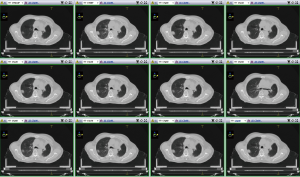

The 24 patients were scanned both in 3D and 4D CT with the same scan range: from the cricothyroid membrane to the costophrenic angle of the inferior margin. The slice thickness was 3 mm. After tumor location scanning was completed, the in-built Brilliance CT software collected the scan information and reconstructed 10-phase CT images for the 4D-CT scan, which were named the following: CT0, CT10, CT20, CT30, CT40, CT50, CT60, CT70, CT80, and CT90. The CT maximal intensity projection (CTMip), minimum intensity projection (CTMinIP), average intensity projection (CTAvgIP), and the CT compilation of CT0 and CT50 (CTExs) were generated according to the 10 phase images. However, if the density of the tumor was greater than that of the lung, the MinIP and AvgIP were considered meaningless. Finally, 3D-CT, 10-phase, Mip, and Exs images were transferred into the Monaco 5.2 treatment planning system. Figure 1 shows one patient’s 10-phase lung images at a fixed slice.